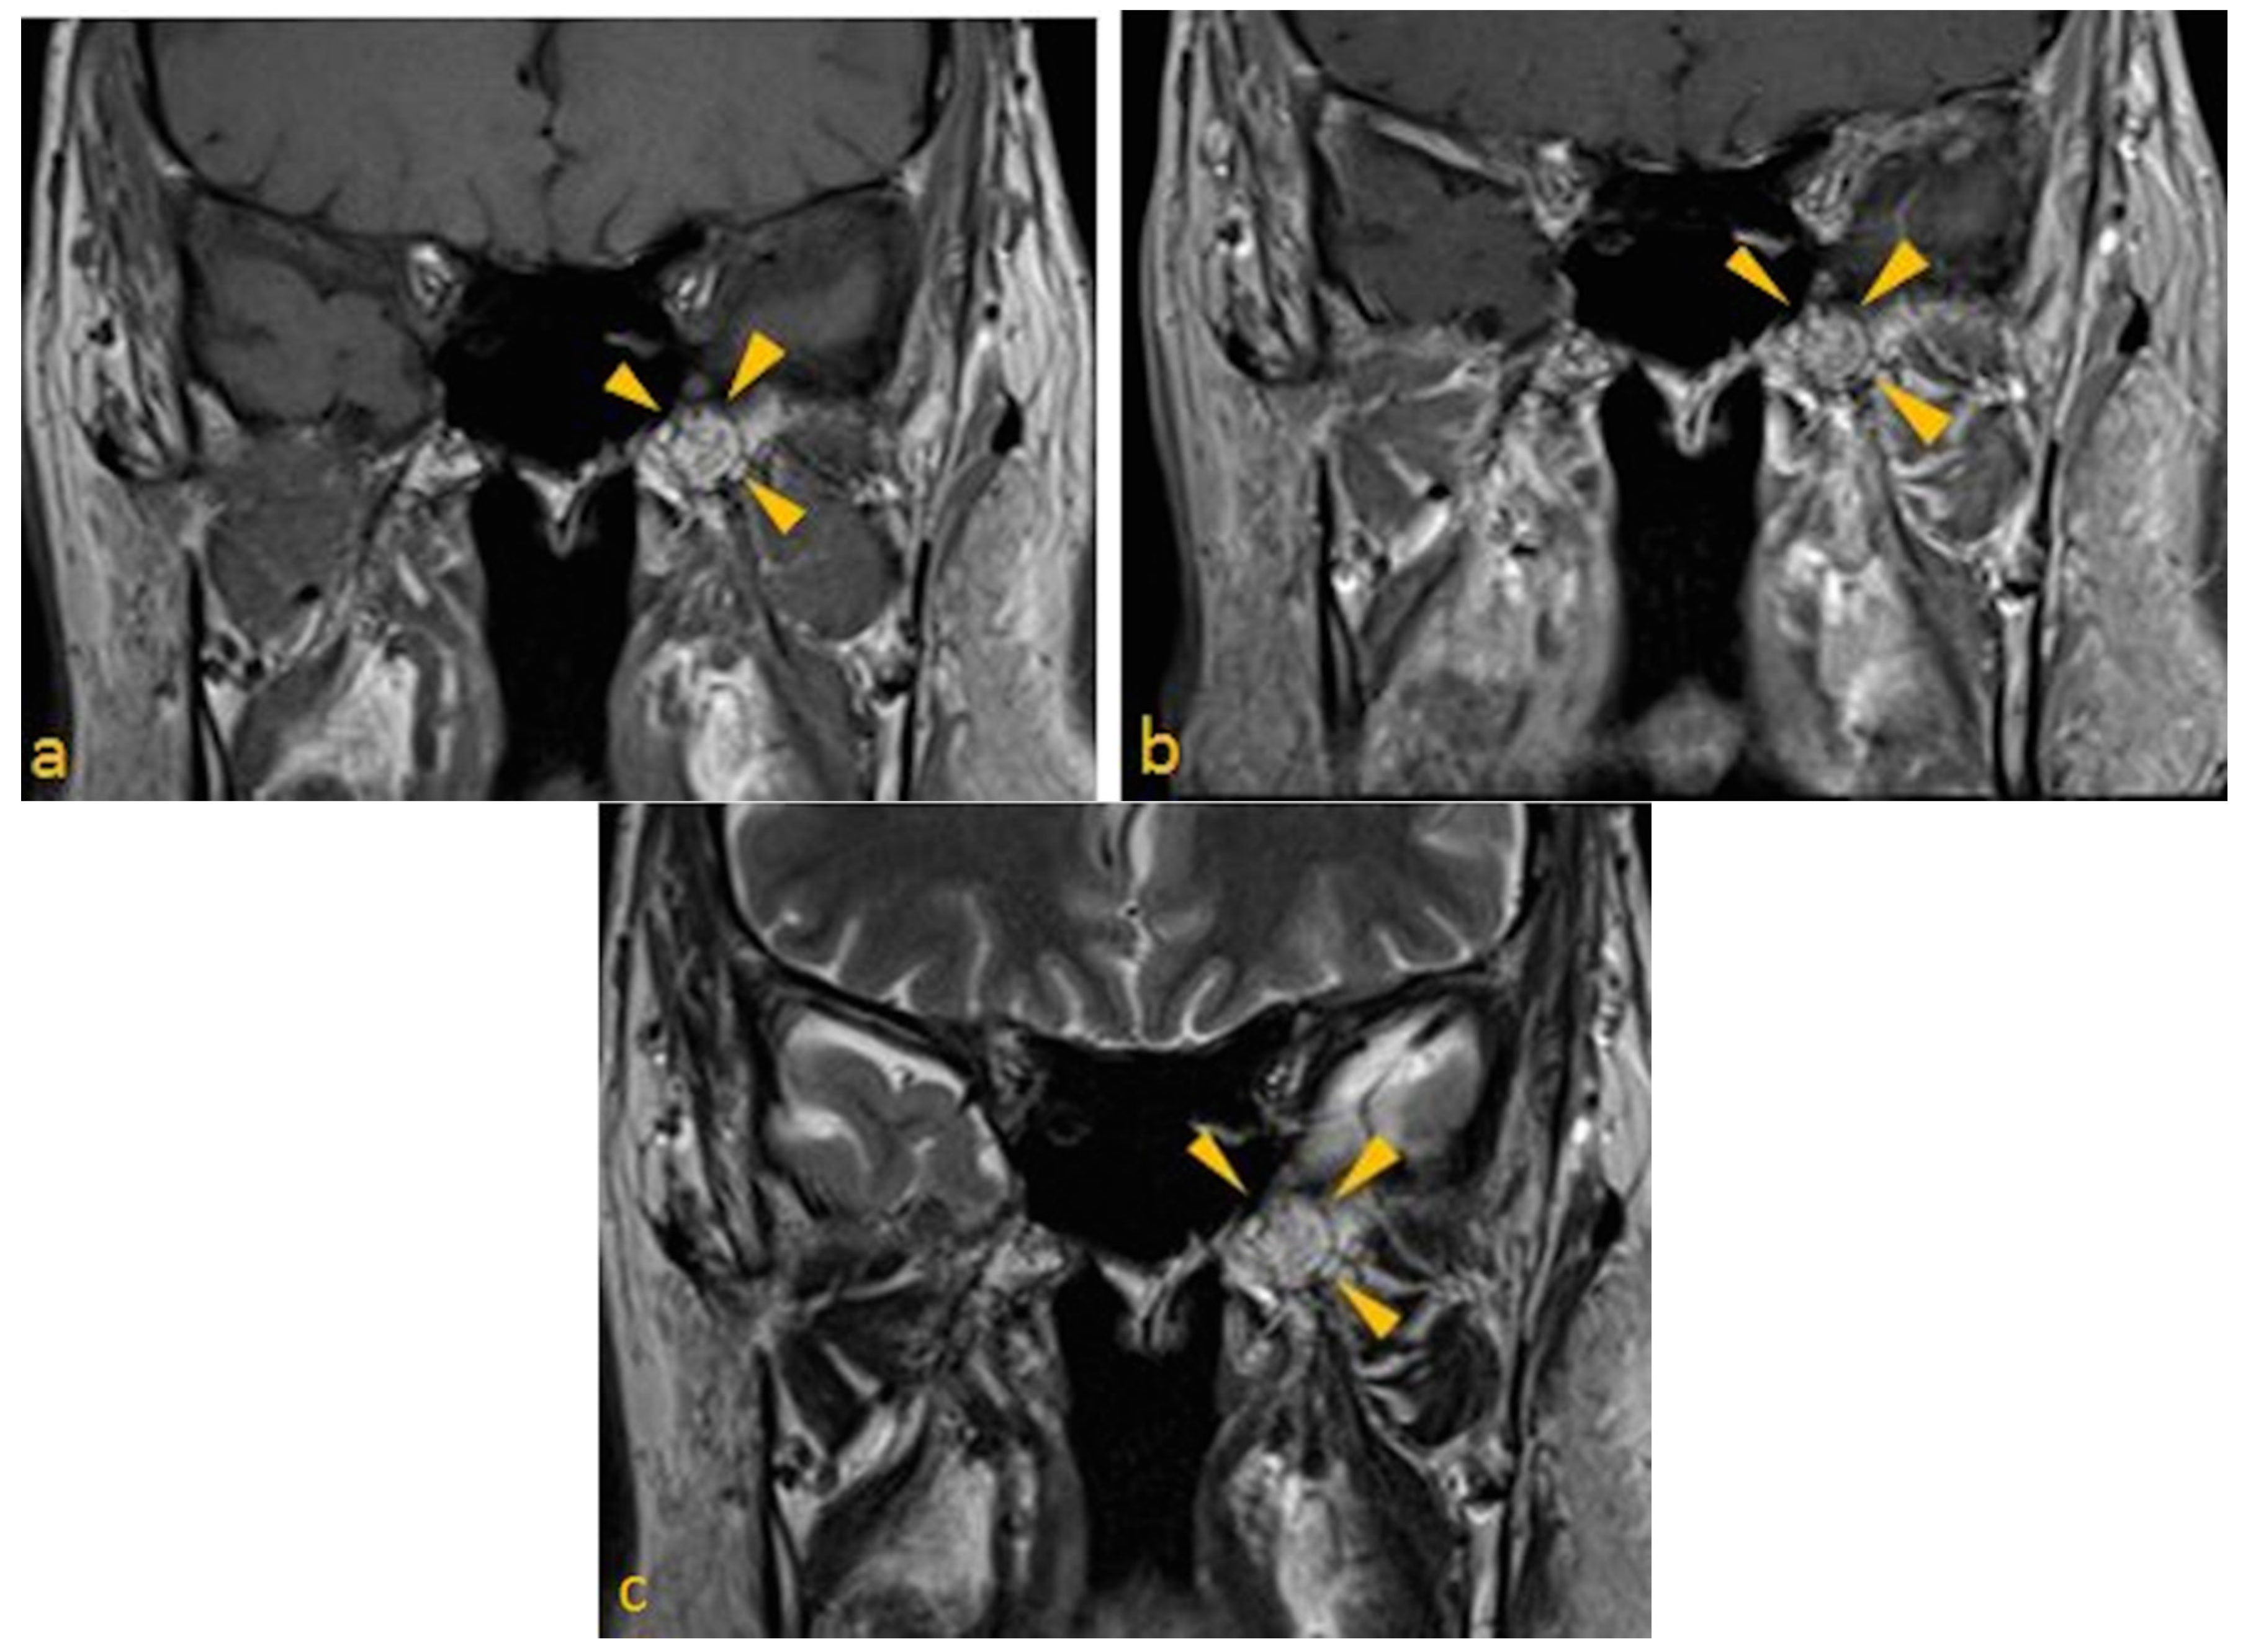

- Lesion must be non-expansile with sclerotic, well-defined margin, and should be located at a site of normal pneumatization. Evidence of fatty content should be present. Internal curvilinear calcifications should be noted on CT images [1].

- Since, sphenoid sinus is closely related to several vital neurovascular structures such as internal carotid artery and optic nerve, any associated skull-base foramina should remain intact and patent.